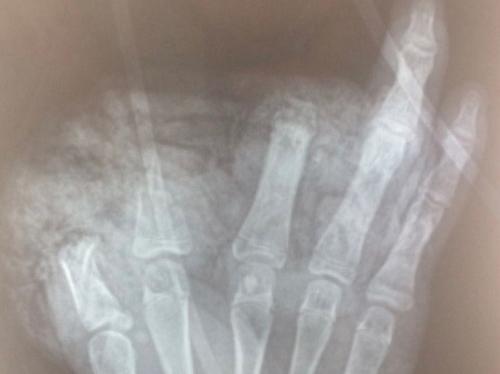

Bệnh nhi tên N.H.A.T. (nam, 14 tuổi), sống tại Trang Hạ, thị xã Từ Sơn, tỉnh Bắc Ninh. Cháu bé được đưa tới cấp cứu tại Bệnh viện Hữu nghị Việt Đức trong tình trạng nhiều xây xát vùng hàm mặt, ngực, bụng; mắt trái rách lớp mi trên, cương tụ kết mạc. Ngoài ra, bàn tay trái của cháu bị dập nát, cụt chấn thương ngón 1,2,3. Vết thương mu tay và gan bàn tay kích thước 10cm, lóc da gan bàn tay cùng nhiều dị vật đen, bẩn.

ThS.BS Đoàn Lê Vinh, Khoa Phẫu thuật Chấn thương chung, Bệnh viện Hữu nghị Việt Đức cho biết, bệnh nhi được phẫu thuật cấp cứu cắt lọc, sửa mỏm cụt ngón 1,2,3; xử lý vết thương phần mềm gan bàn tay, mu bàn tay và nhiều vị trí thương tổn khác. Ca phẫu thuật diễn ra trong 1 tiếng đồng hồ.

Sau mổ, tình trạng bệnh nhi ổn định, băng thấm dịch ngón 4,5 hồng ấm. Với vết thương mi trên và kết mạc, cháu T. được chuyển sang bệnh viện chuyên khoa mắt để tiếp tục điều trị.